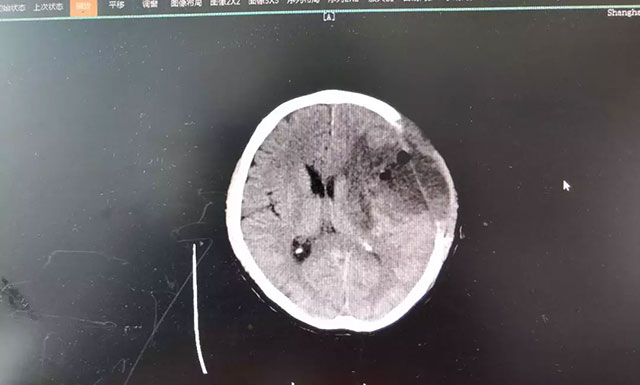

“是不是中風(fēng)了?”家人看情況不妙,趕緊將錢先生送到當(dāng)?shù)蒯t(yī)院檢查。CT影像報(bào)告顯示,患者大腦左顳葉占位。隨后幾天,錢先生的癥狀出現(xiàn)反復(fù)和惡化,考慮到當(dāng)?shù)蒯t(yī)療資源條件較為有限,家人將其轉(zhuǎn)至上海藍(lán)十字腦科醫(yī)院,作進(jìn)一步診斷治療。

在藍(lán)十字腦科醫(yī)院,頭顱磁共振增強(qiáng)掃描影像進(jìn)一步明確:錢先生左額顳葉占位性病變,類橢圓形團(tuán)塊狀異常信號(hào)大小約4.3*3.2cm,邊界不清,病灶周圍有明顯水腫。從癥狀體征和影像學(xué)資料判斷,錢先生患上腦膠質(zhì)瘤的可能性很大,通過對(duì)患者術(shù)后病理標(biāo)本檢驗(yàn),也印證了該結(jié)論!